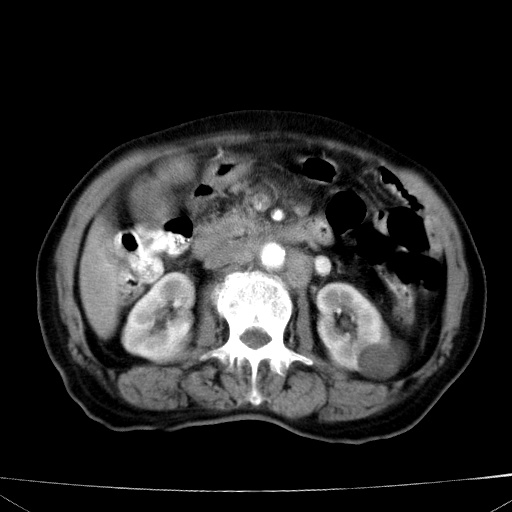

网站人气太旺!昨天的帖子就沉到海底,只好再发贴!ct18338:女 78岁,肝胆病变,已增强,再会诊!原帖链接:http://www.radida.com/bbs/forum.php?mod=viewthread&tid=50032

1)考虑胆囊癌侵犯肝脏并肝门区、腹膜后及右侧膈角后淋巴结转移。2)肝左叶近肝顶部囊肿。3)肝左叶肝内胆管结石。4)左肾近下极囊肿。

1)考虑胆囊癌侵犯肝脏并肝门区、腹膜后及右侧膈角后淋巴结转移。2)肝左叶近肝顶部囊肿。3)肝左叶肝内胆管结石。4)左肾近下极囊肿。支持